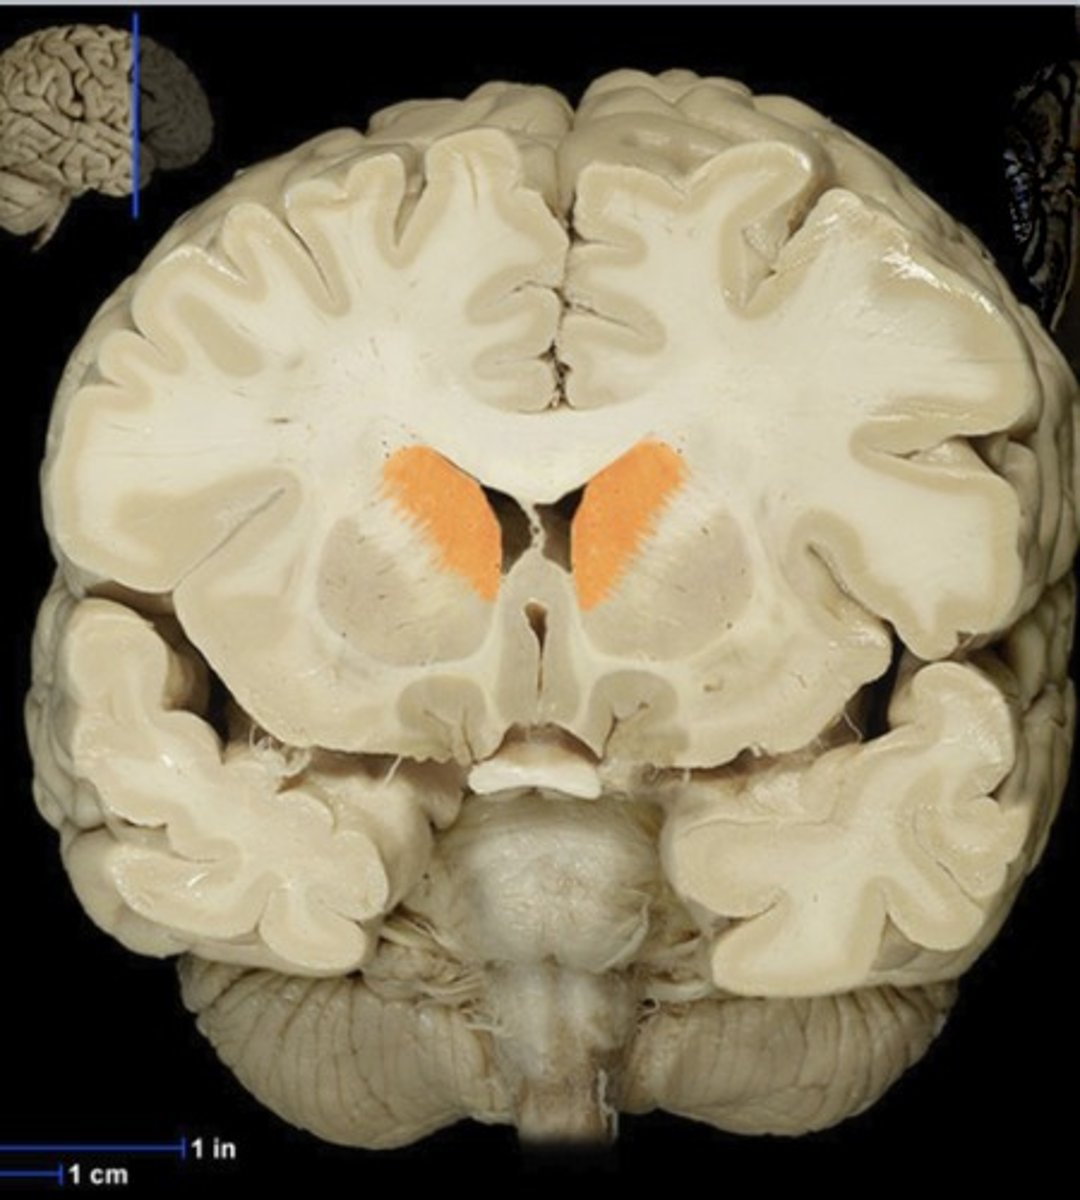

Caudate Nucleus

Name this structure

Fornix

Name this structure

Lateral Ventricles

Name this structure